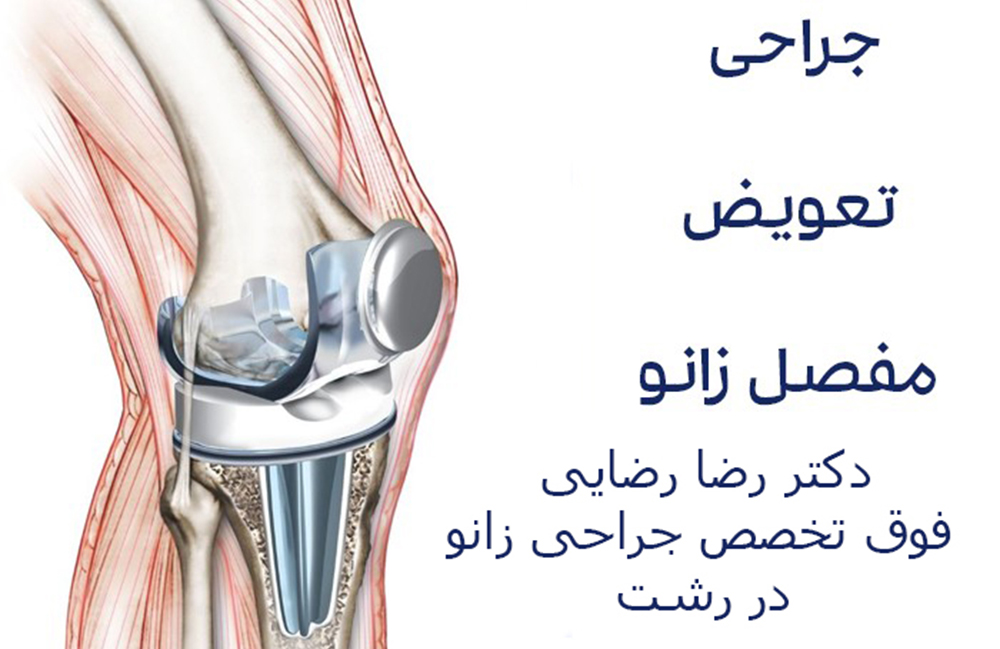

- تعویض مفصل در موارد پیشرفته آرتروز

زمانی که آسیبهای ساختاری شدید مانند پارگی رباطها، بیثباتی قابلتوجه مفصل پیشرفته وجود داشته باشد، درمان جراحی بهترین گزینه محسوب میشود. جراحی ممکن است بهصورت آرتروسکوپی (کمتهاجمی) یا جراحی باز انجام شود تا ساختارهای آسیبدیده ترمیم یا بازسازی شوند. بازسازی رباط صلیبی به بازگرداندن ثبات زانو کمک کرده و اصلاح مشکلات کشکک باعث بهبود حرکت طبیعی مفصل میشود. در موارد پیشرفته که مفصل بهشدت تخریب شده است، تعویض مفصل زانو میتواند درد را کاهش داده و توانایی حرکت بیمار را بهطور قابلتوجهی بازیابی کند.

بررسی تخصصی توسط پزشک باتجربه نقش کلیدی در انتخاب بهترین روش درمان دارد. دکتر رضا رضایی، فوق تخصص جراحی زانو در رشت و متخصص ارتوپد، با بهرهگیری از روشهای نوین تشخیصی و درمانی، امکان درمان دقیق و بازگشت عملکرد طبیعی زانو را برای بیماران فراهم میکند.